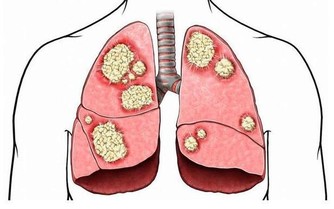

胃癌就是胃部的惡性腫瘤,此病在我國是惡性腫瘤榜首,常發生於50歲以上男性患者。

如果是胃癌早期,治療效果還好,但是,很多胃癌被發現時已是晚期,只能對症處理,盡力延長生命、減輕痛苦,所以早發現很重要。